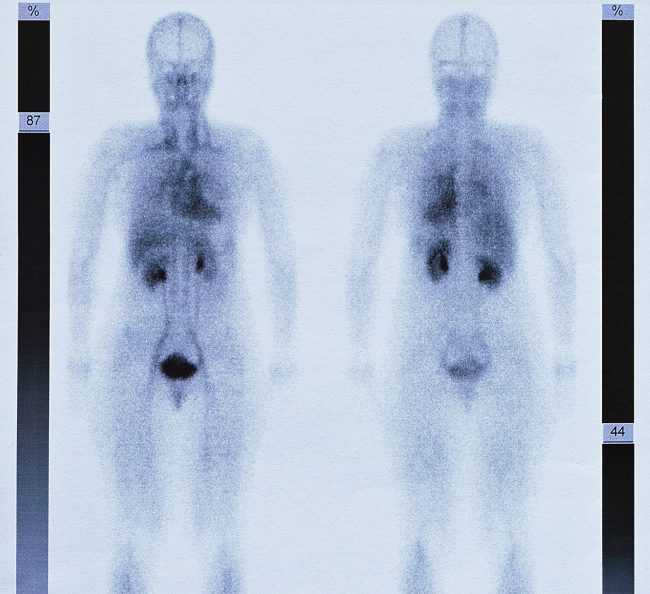

Skelettszintigraphie

Die Skelettszintigrafie (auch Knochenszintigrafie genannt) ist eine nuklearmedizinische Untersuchung, mit der sich Knochen und deren Stoffwechsel begutachten lassen. Anhand des Beschwerdebildes wird der Untersuchungsablauf individuell festgelegt. Hierzu wird vor der Untersuchung ein ärztliches Gespräch mit dem Patienten geführt. Im Gegensatz zu den radiologischen Verfahren, wo lediglich einzelne Körperabschnitte untersucht werden können, ist es mit der…